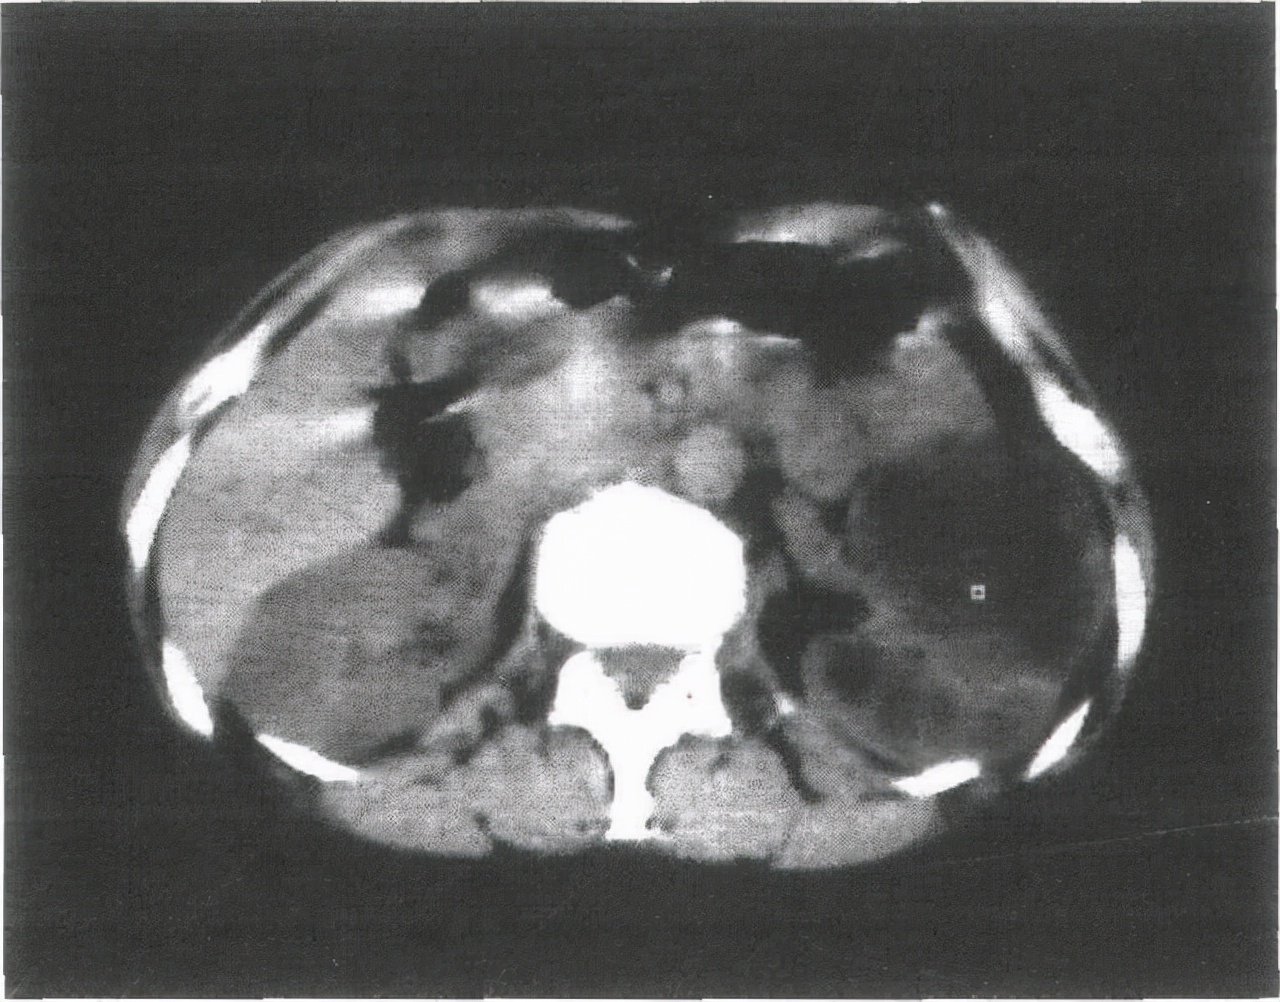

钙造化是指超声扫描时,在某个器官观察到的形态不规则,类似结石的钙质沉淀,检查图像显示 为白色亮斑,专业术语叫“强回声”。

钙化灶能够出现在身体的各个部位, 特别是在乳腺,甲状腺,子宫,肺部,前列腺等部位会引起钙化的疾病也特别多 ,良性和恶性疾病都有一定的可能。所以在体检时若是查出身体某些部位出现钙化,第一时间不要太过担心,可以找医生咨询一下,再根据临床症状结合 进一步检查作出准确的判断后,再针对性的进行治疗。